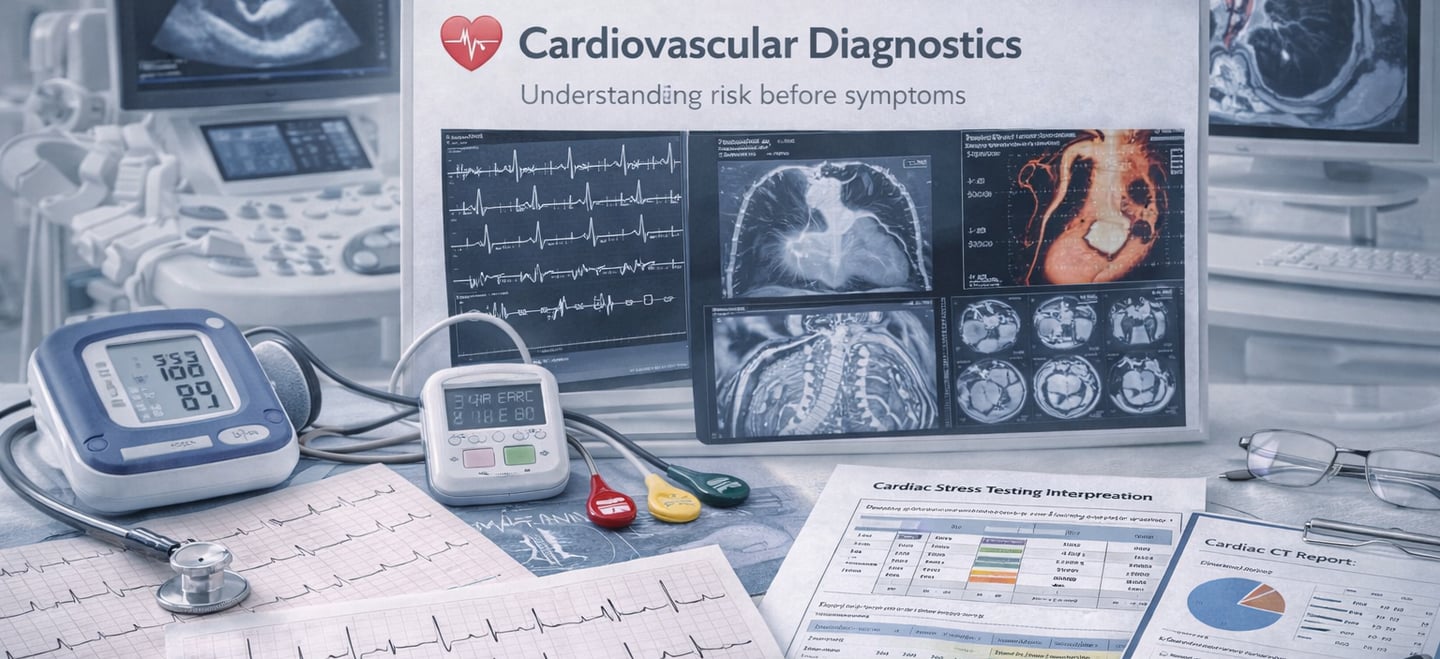

❤️ Cardiovascular Diagnostics

Understanding risk before symptoms

ECG / EKG interpretation

Holter monitoring

Echocardiography

Stress testing (exercise & pharmacologic)

Cardiac CT (calcium scoring, CTA)

Cardiac MRI

Ambulatory blood pressure monitoring